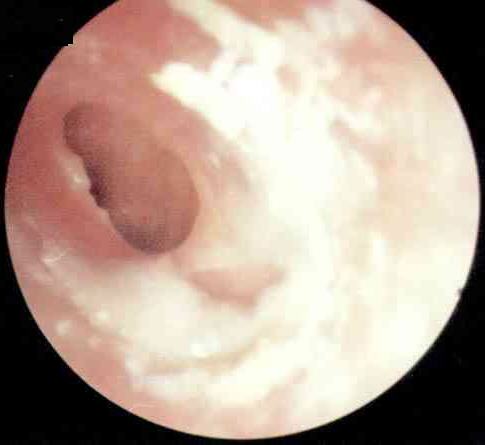

中耳炎病理图

西安中大耳鼻喉医院耳病诊疗中心张全安教授介绍,对于耳朵流脓,许多人都认为没什么了不起,是小毛病。但事实上,由于人的耳部与头颅内的脑膜很接近,中耳若感染发炎,可以通过血液循环或是通过内耳直接扩展到颅内,而引起颅内的并发症,严重时可以危及患者的生命安全。经过检查发现,刘先生属于化脓性中耳炎,病灶已侵犯到脑部造成脑脓肿从而导致头部剧烈疼痛,这个时候如果脓肿破裂则随时有生命危险。随后冯亮医生为他实施“”,有效解除了隐患。